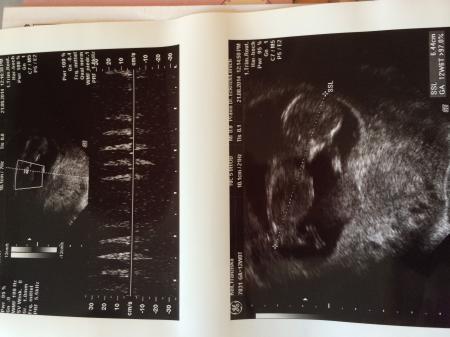

Alles bestens :-) Die Erdnuss ist 6,4 cm groß und nackenfalte auch unauffällig . Also alles so wie es sein soll Bin seit heute auch in der 13. Woche und hoffe das die leichte noch vorhandene übelkeit auch bald weg ist . Ich wünsche euch allen noch einen tollen Tag und ein tolles Wochenende Ich werd dann mal shoppen gehen

Danke ihr seid echt goldig Hier noch das Bildchen

Bild zu